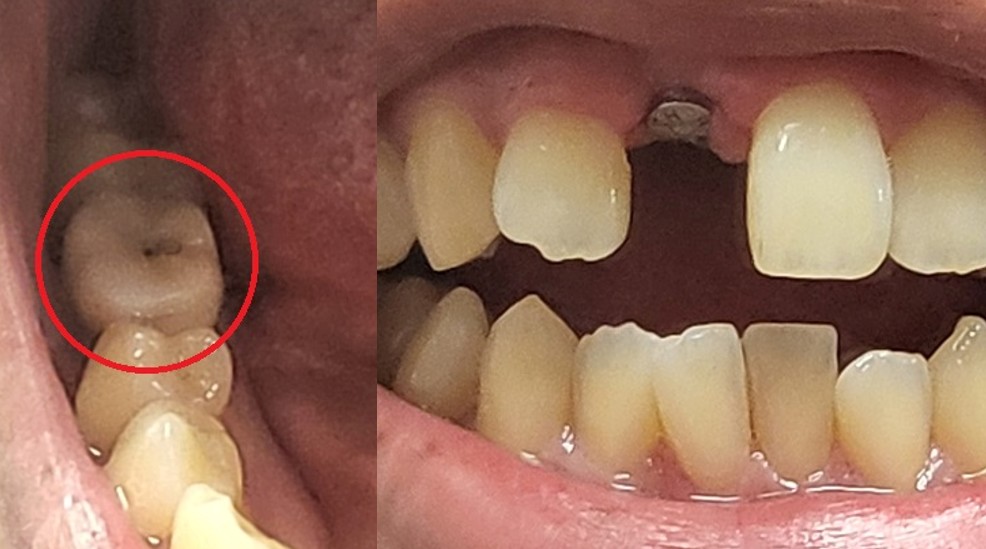

반면 최근에 추가로 앞니 임플란트 치료를 진행하였는데 지금은 85만원이 발생했습니다.

- 앞니는 임시 가짜 치아를 심지 않았다. (빠진 채로 다닙니다. 아래 사진 참조)